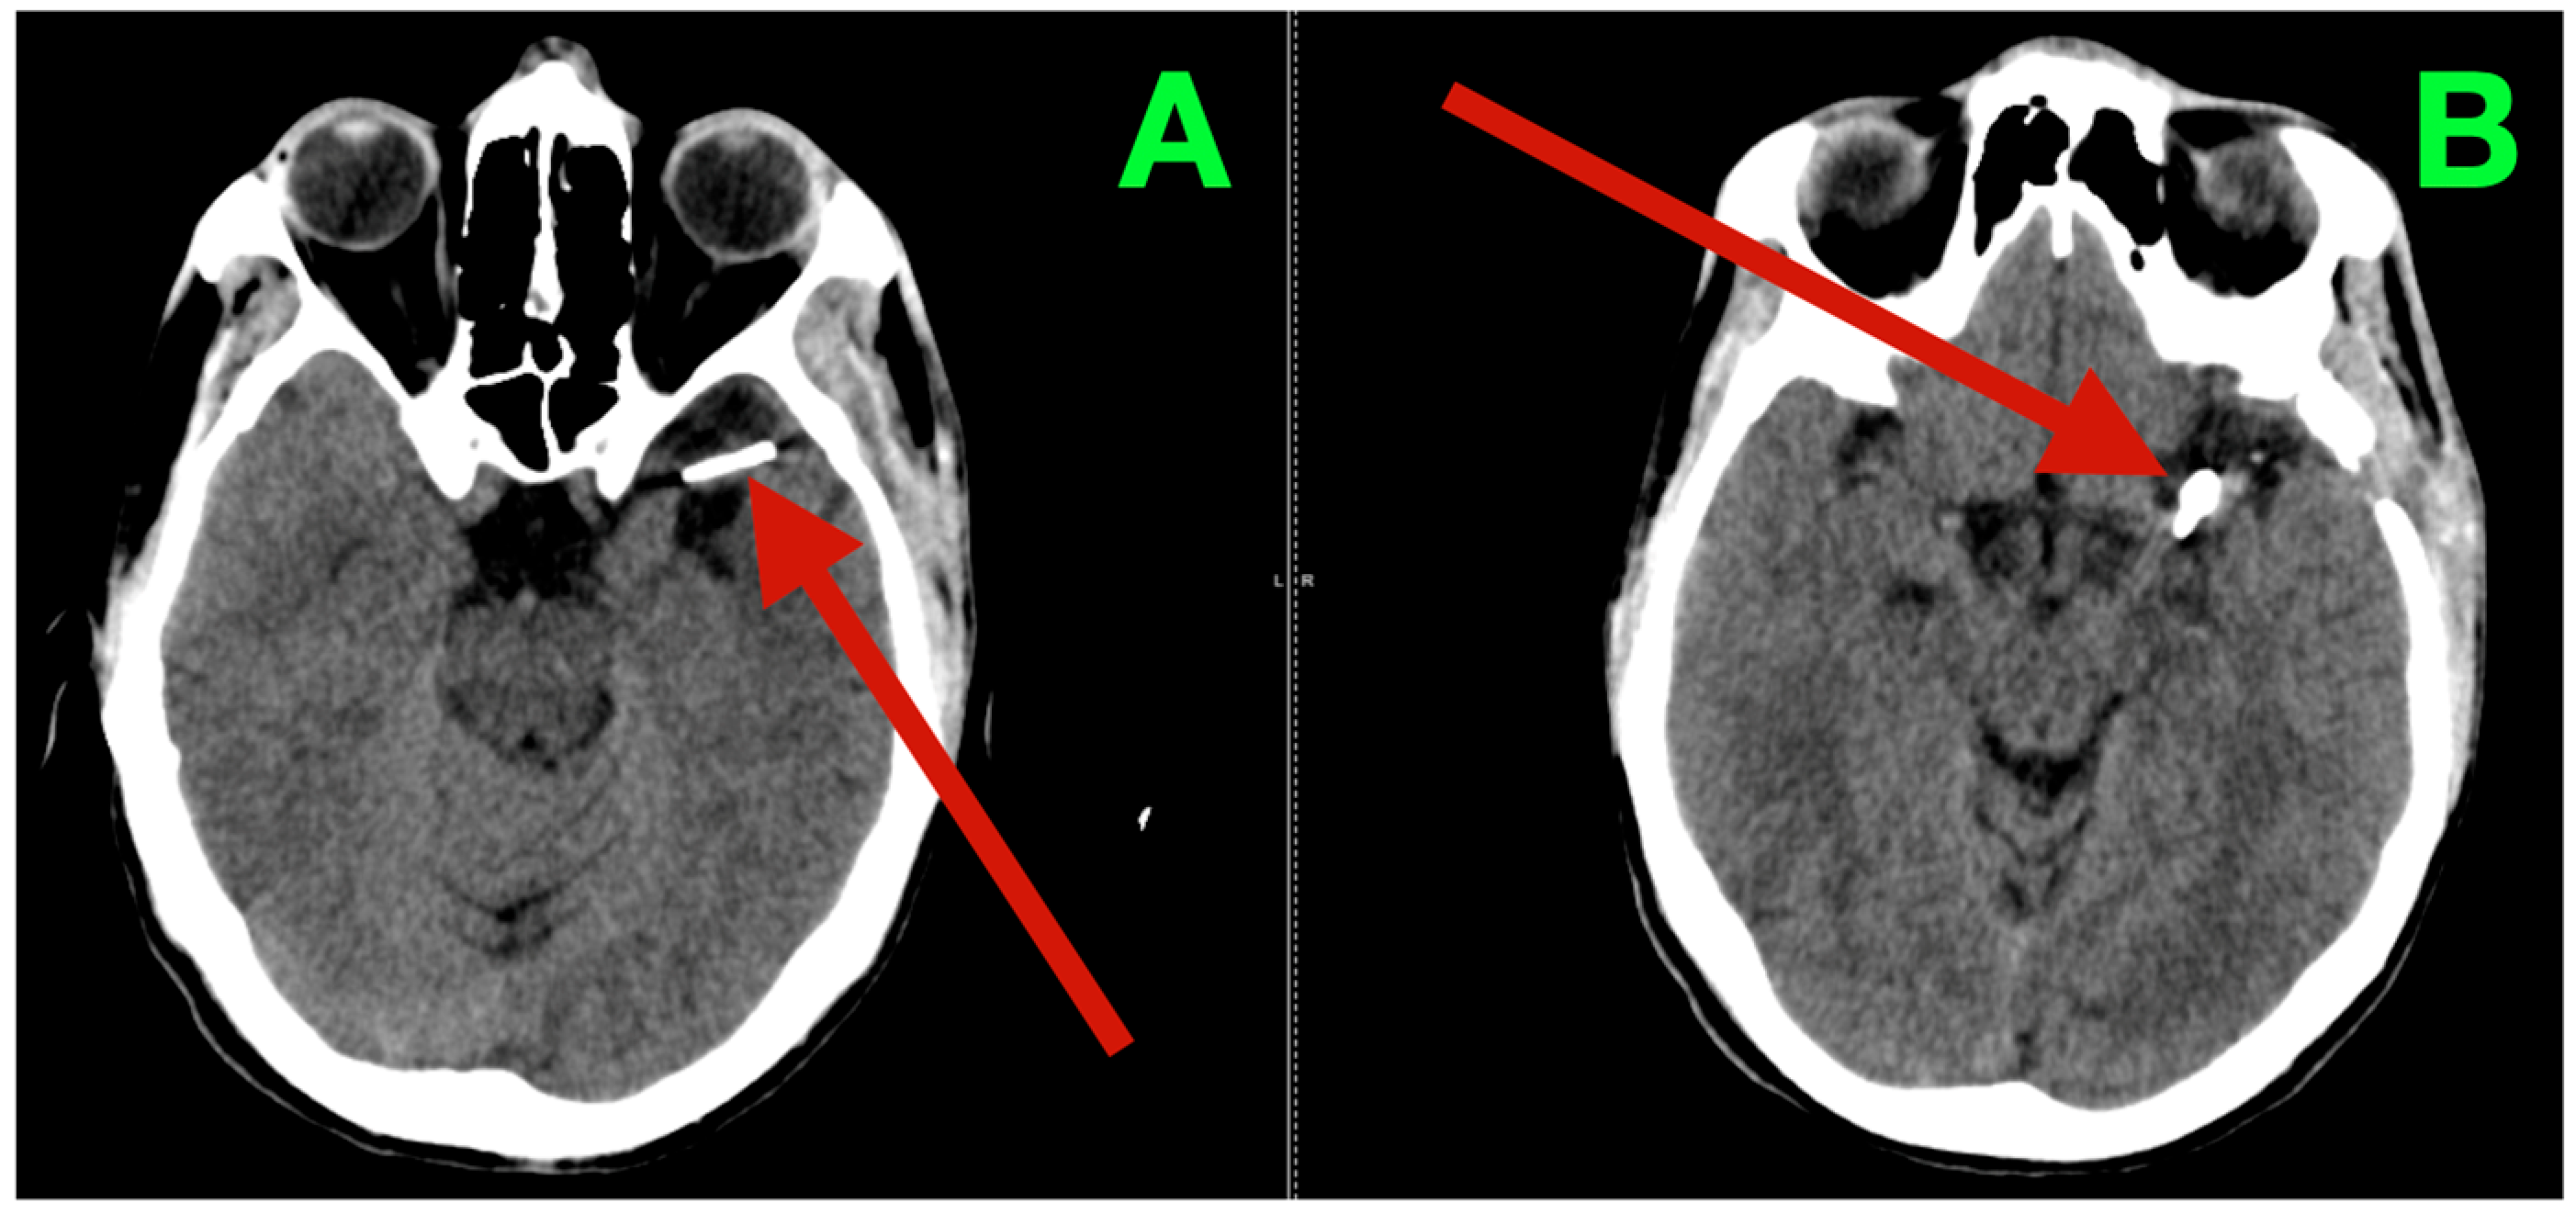

2.3. Three-Dimensional Rotational Angiography (3DRA) and CTA Reconstruction

High-resolution 3D rotational angiographic volumes were collected, and volumetric rendering and CTA were undertaken (Figure 2A–D). This reconstruction optimally adapted to isolate the traditional overlap of vessels or planar angiography and enabled surgical simulation. Additionally, it offered analysis of neck geometry, dome orientation, and angles of take-off of the branches in orthogonal planes, along with great detail to preoperative planning, discarding a virtual “clip trajectory” workable area. The anterosuperior projection of the bifurcation aneurysm was again confirmed, with the dome axis pointing toward the mid-insular cortex. The superior M2 trunk had a narrow angle of take-off at 54° from the superior neck border, while the inferior trunk originated in a more posterior and inferior orientation with a 68° angle that created an acute “tight fork”. This neck geometry significantly reduced tolerance for misalignment of the clip blade because even slight decreases in alignment can add a partial increase in compromise of the lumen—especially if the clip was aligned in a position that would yield a submillimeter misalignment. The neck contained 1.8 mm of orifice from the superior M2 and 1.4 mm of orifice from the inferior M2, as calculated on centerline flow reconstruction. The perforator anatomy of the M1 fusiform aneurysm was elaborated upon with remarkable fidelity. The lenticulostriate had explicitly dissipated perpendicularly on the dorsal wall with their immediate posterior vector direction of the perforated substance. The two biggest perforators measured 460 μm and 420 μm at their origins and were tapering quickly within 1.2 mm of take-off. This made both arteries very sensitive to even glass-like movement in the parent vessel from the clip applied to the bifurcation lesion. The inter-aneurysmal distance was short at 4.7 mm, which allowed for potential mechanical manipulation of the other vessel even if we only performed the dissection on one lesion.

Figure 2.

Three-dimensional rotational angiography and CTA volumetric reconstruction of the left MCA complex. (A) 3DRA, left internal carotid artery injection, anterolateral oblique projection. The bifurcation aneurysm arises at the M1 division point, with the broad neck partially incorporating both superior and inferior M2 origins. Note the anterosuperior dome projection toward the mid-insular cortex and the tight angular divergence of the M2 trunks (“tight fork” configuration), leaving minimal tolerance for clip blade malrotation. (B) 3DRA, orthogonal craniocaudal projection. The dome’s spatial relationship to the superficial Sylvian venous complex is evident, with the shortest opercular vein lying within 3 mm of the aneurysmal wall. The fusiform M1 dilation is visible proximally on the dorsal surface, directly within the lenticulostriate perforator belt. (C) CTA bone–vascular fusion, lateral projection. Depth mapping from the sphenoid ridge shows the bifurcation aneurysm positioned approximately 17 mm deep, corresponding to the mid-third Sylvian fissure corridor, while the fusiform aneurysm lies deeper (~23 mm), just proximal to the genu of the MCA. (D) CTA bone–vascular fusion, inferolateral projection. The lenticulostriate perforators arising from the fusiform M1 segment are visualized with submillimetric resolution, demonstrating perpendicular dorsal take-off toward the anterior perforated substance, underscoring the extreme vulnerability of these vessels to even minimal parent vessel displacement during bifurcation clip application.

Bone surface reconstruction suggested that the bifurcation aneurysm was situated approximately 17 mm deep to the sphenoid ridge, corresponding to the origin of the Sylvian fissure at or near the mid-third Sylvian fissure exposure, while the fusiform aneurysm was much deeper at 23 mm from this same cortical surface landmark, and just proximal to the genu of the MCA.